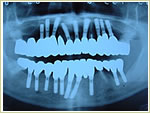

◆崩壊咬合治療症例

症例1 32歳 男性 画像拡大

治療前 治療後